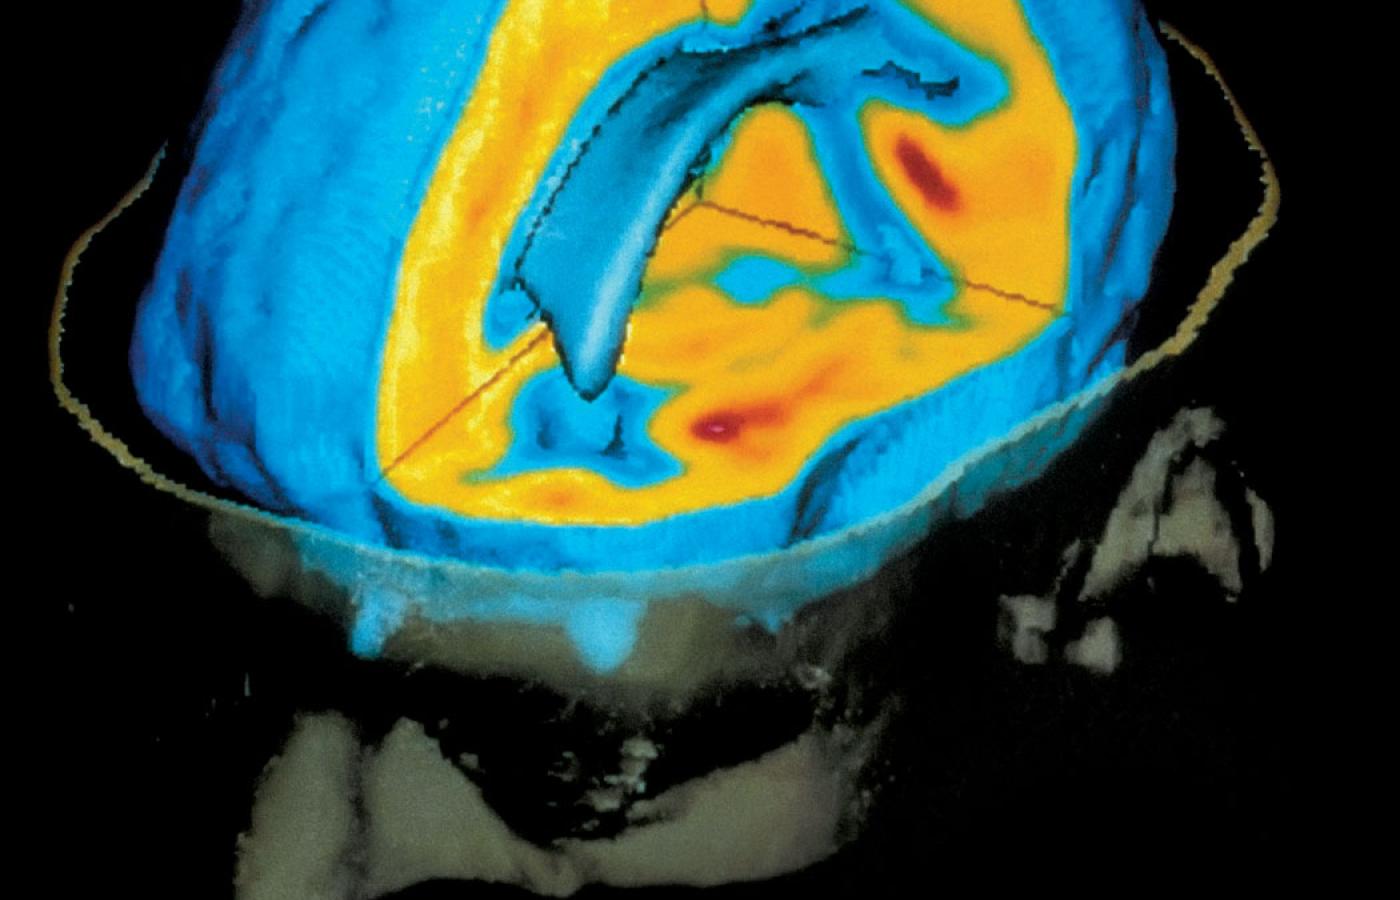

Upowszechnienie neuroobrazowania w latach 90. ubiegłego wieku przyczyniło się do poszerzenia wiedzy o ludzkim mózgu w kilku aspektach. Upowszechnienie neuroobrazowania w latach 90. ubiegłego wieku przyczyniło się do poszerzenia wiedzy o ludzkim mózgu w kilku aspektach. nimon_t / Smarterpix/PantherMedia

Komputerowe analizy danych pochodzących ze skanerów mózgu zawierają błędy.Steger Photo/Getty Images Komputerowe analizy danych pochodzących ze skanerów mózgu zawierają błędy.

Czym jest fMRI? Metoda ta zaczęła być powszechnie stosowana przez naukowców w latach 90. XX w., a swoją popularność zyskała dzięki możliwości bezinwazyjnego zaglądania do mózgu człowieka i przypatrywania się jego aktywności w trakcie np. rozwiązywania jakichś problemów czy oglądania zdjęć ukazujących przemoc.

Tym, co owe urządzenia bezpośrednio mierzą, nie jest jednak aktywność elektryczna komórek nerwowych, tylko sygnał zależny od poziomu nasycenia tlenem krwi (w skrócie BOLD, od blood-oxygen-level-dependent). Pomiar taki jest możliwy, gdyż utlenowana krew reaguje na silne pole magnetyczne wytwarzane przez potężne magnesy skanera.

Zasada działania jest tu stosunkowo prosta: obszary mózgu, które zaangażowane są w wykonywanie jakichś zadań, pracują intensywniej i z tego powodu zgłaszają zapotrzebowanie na więcej „paliwa”, czyli właśnie tlenu.